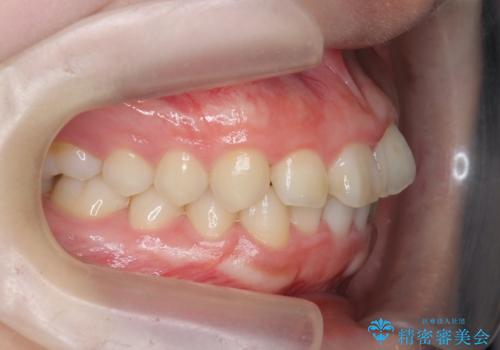

前歯の見た目を改善したい

- ねじれの目立つ前歯の見た目を改善したいと矯正治療を希望され来院されました。

がたつきの改善をマウスピース矯正インビザラインで行っていきます。

ガタつきの改善はもちろん、歯列全体のアーチも放物線状にきれいに排列し審美性を向上させることができました。